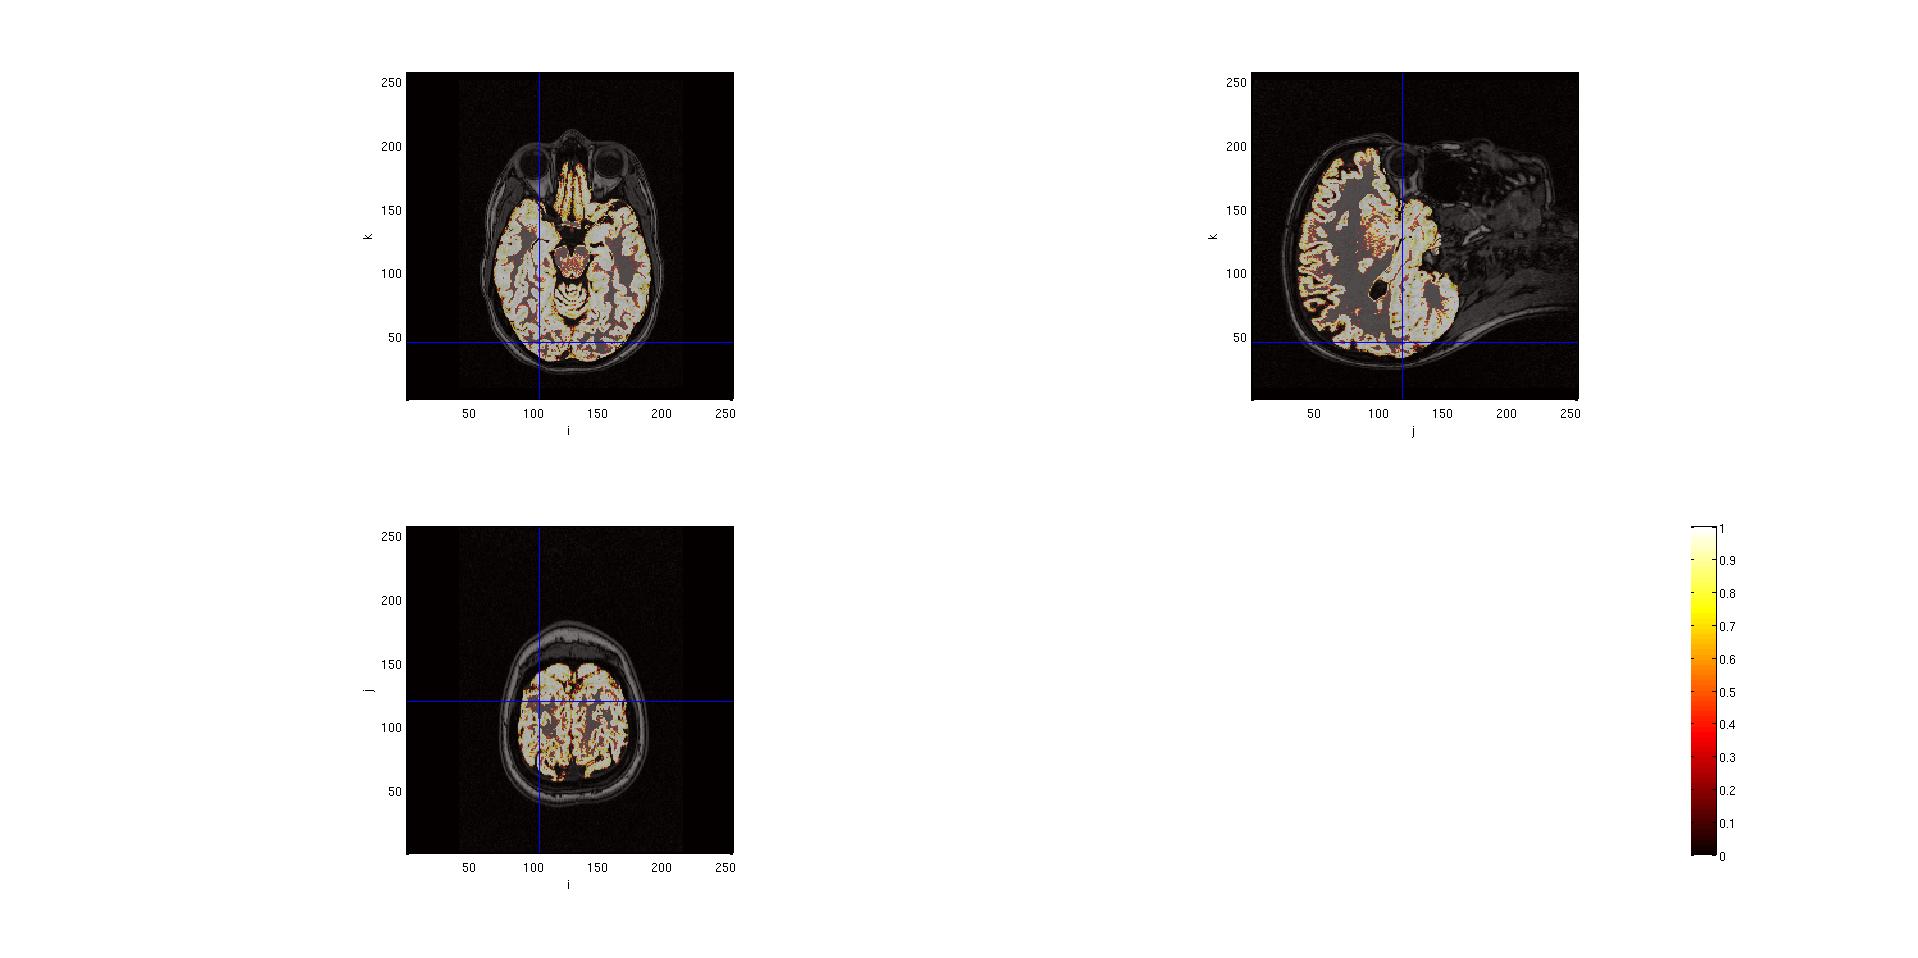

With this kind of segmentation, the output is the identification of the gray matter, the white matter and the cerebro-spinal fluid on the images. It is possible to look at the results of this segmentation.

seg.anatomy = mri.anatomy;

cfg = [];

cfg.funparameter = 'gray';

%or

%cfg.funparameter = 'white';

%cfg.funparamter = 'csf';

cfg.interactive = 'yes'; %(this allows to click on the images in order to see other slices

ft_sourceplot(cfg, seg);

Here are the outputs of ft_volumesegment on data from a .mgz volume, plotted with ft_sourceplot.

seg.gray